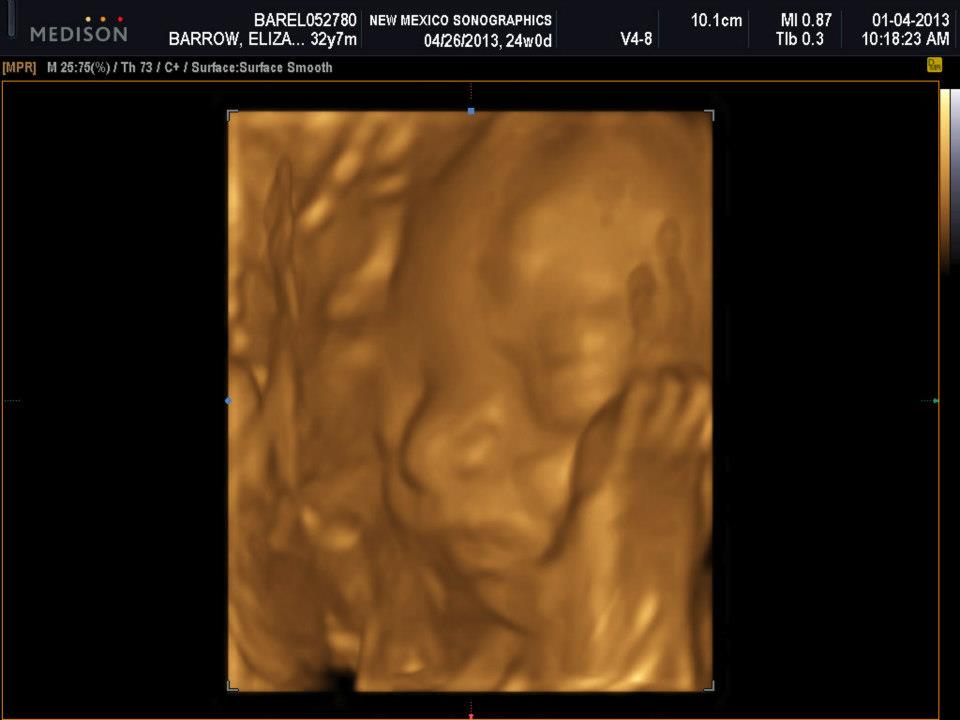

Mike came along to see our little girl in action. It was nice because they had a huge screen on the wall so he could watch everything going on. The girl did the usual 2D ultrasound where you see the basic makeup of the baby and then she turned on the 3D scan. Here are some of the shots we got:

Mike and I were laughing because her hand looks like a foot. I even made a comment about it and she said the baby moved right when they took the picture. You can kind of tell on the right hand side where her hand was.